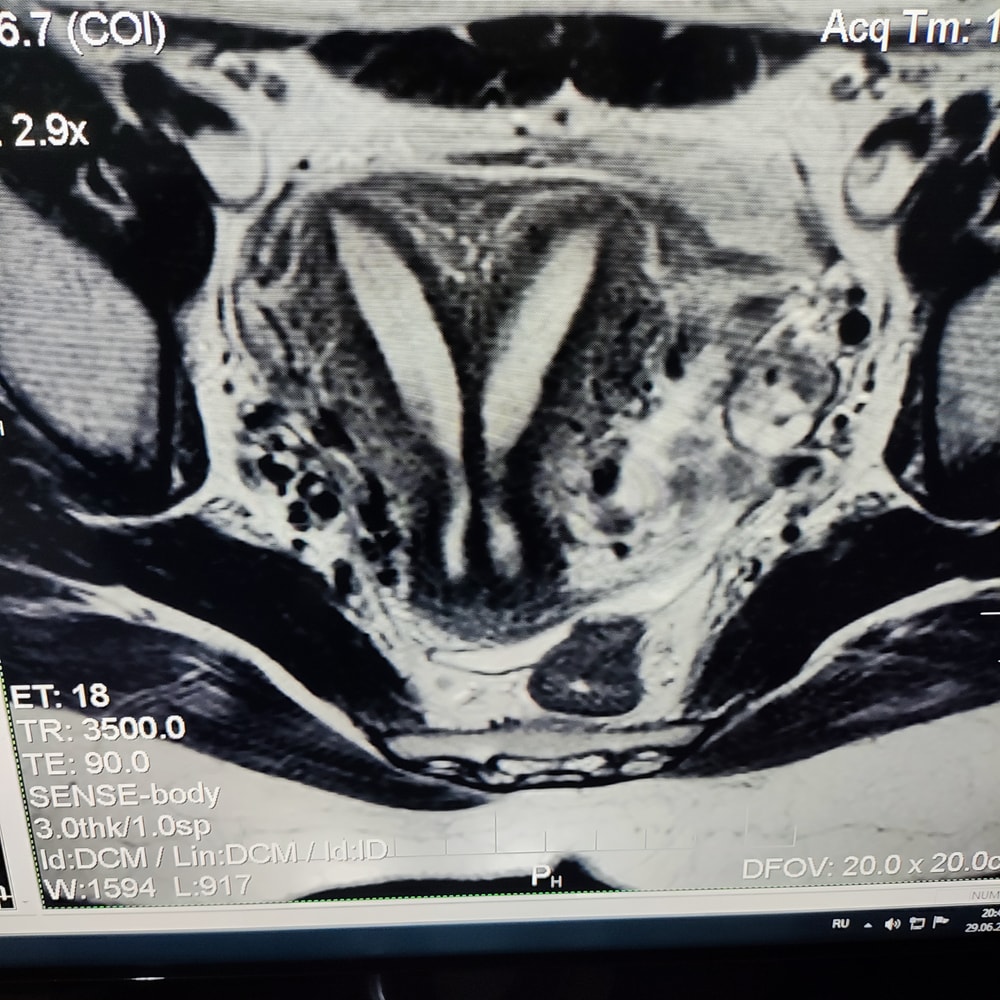

У меня удвоение / двурогая матка (мнение врачей разное) на данный момент первая Б, 5 недель. До этого долго не получалось и меня хотели направить на пластику матки (тут сложнее, чем просто перегородку убрать)

Вот старое МРТ

Чего ожидать, не знаю)